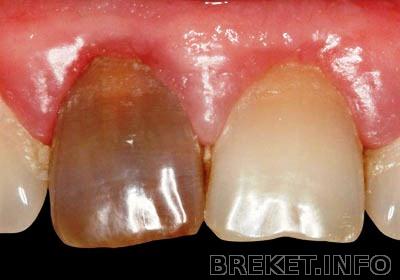

РФ, красный зуб, red russian, это все синонимы - резорцин формалинового метода лечения зубов (спасибо нашей стоматологии). Зуб по сути в мумию превращают, где связка отмирает и зуб припаивается к кости.

РФ зуб удивил!!! Ничего не поняла, можно подробнее про него, интересно! Это хорошо или плохо?

ЮлияHowes Современная стоматология считает, что это плохо и мина замедленного действия. А в СССР это было ноу-хау - пришел чел в клинику, без волокиты вскрыли пульпу , чуть поковырялись, закинули туда резорцин-формалиновую смесь и все там в мумию превратилось и не болит. Ни надо рентген делать, проверять как пройдены каналы, гуттаперчей их пломбировать. Одним словом сказка для врача. А то что зуб по сути мумия - стеклянного типа, и связка зубная склеротизировалась, и формалин плавно отравляет организм, и каналы потом задолбаешься проходить это пофиг.

Вот как они выглядят -

Сам прикол, что до сих пор этим способом кое где лечат